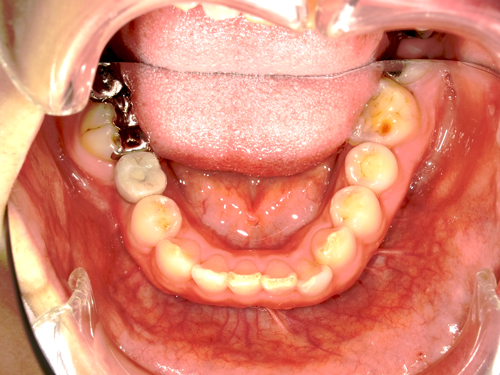

歯を失ってから長期間経っていたり、もともと骨の量が不足している場合でも、インプラントを埋め込む前に骨を移植して骨の量を増やす処置を行えばインプラント治療を受けることができます。

歯を失うと、咀嚼の刺激が顎に伝わらなくなるため、顎の骨が少しずつ痩せてしまいます。

インプラントは、入れ歯やブリッジとは違い、歯だけでなく歯根も取り戻せるため、顎の骨が痩せる(吸収する)のを防ぐことが可能です。